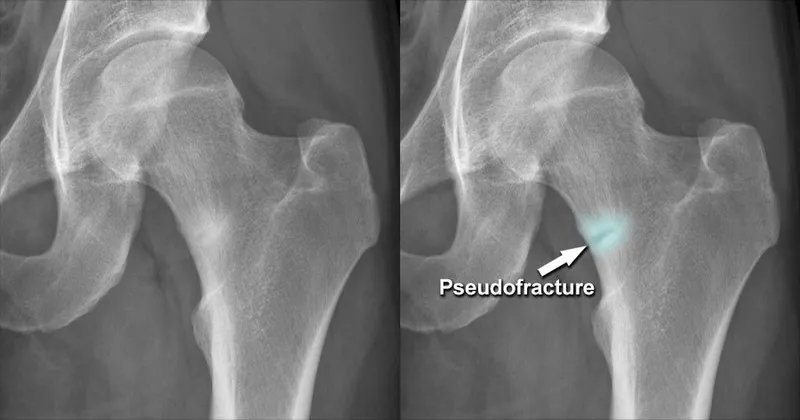

⭐ Looser's zones (pseudofractures) are hallmark stress fractures in osteomalacia, often bilateral and symmetrical, typically seen in scapulae, ribs, pubic rami, and femoral necks.

- Looser's zones (pseudofractures): Hallmark; incomplete transverse radiolucencies. Sites: femoral neck, pelvis, scapula.

⭐ Looser's zones (Milkman's fractures), pathognomonic for osteomalacia, are often bilateral, symmetrical stress fractures through demineralized bone cortex.